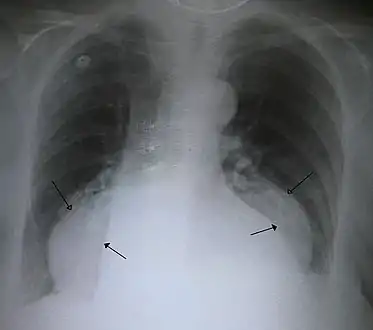

The diagnosis of a hiatal hernia is typically made through an upper GI series, endoscopy, high resolution manometry, esophageal pH monitoring, and computed tomography (CT). Barium swallow as in upper GI series allows the size, location, stricture, stenosis of oesophagus to be seen. It can also evaluate the oesophageal movements. Endoscopy can analyse the esophageal internal surface for erosions, ulcers, and tumours. Meanwhile, manometry can determine the integrity of esophageal movements, and the presence of esophageal achalasia. pH testings allows the quantitative analysis of acid reflux episodes. CT scan is useful in diagnosing complications of hiatal hernia such as gastric volvulus, perforation, pneumoperitoneum, and pneumomediastinum.[8]